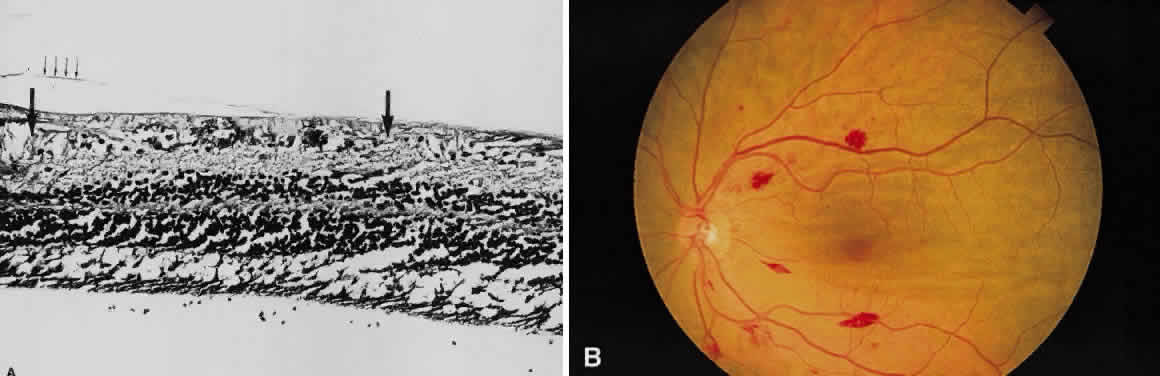

Fig. 17. A. A histologic section stained with H & E demonstrating vascularized

membranes on the disc and retina. Tractional retinal detachment is present. Notice

the subretinal fluid (amorphous eosinophilic material). B. Fundus photograph of fibrous tissue emanating from the disc in patient

with proliferative diabetic retinopathy. The disc is pale; the macula

is edematous with exudate. Pigmented laser spots are visible temporally. Fig. 17. A. A histologic section stained with H & E demonstrating vascularized

membranes on the disc and retina. Tractional retinal detachment is present. Notice

the subretinal fluid (amorphous eosinophilic material). B. Fundus photograph of fibrous tissue emanating from the disc in patient

with proliferative diabetic retinopathy. The disc is pale; the macula

is edematous with exudate. Pigmented laser spots are visible temporally.